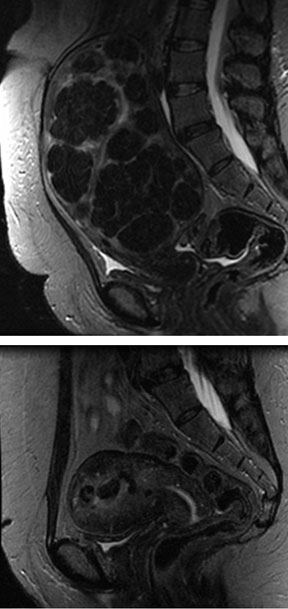

47-year-old woman with severe menorrhagia and pelvic pain underwent UFE. Following the procedure, her menstrual bleeding and pain improved dramatically. The second MRI taken 4 months after UFE demonstrates marked decrease in uterine fibroid tumor bulk.